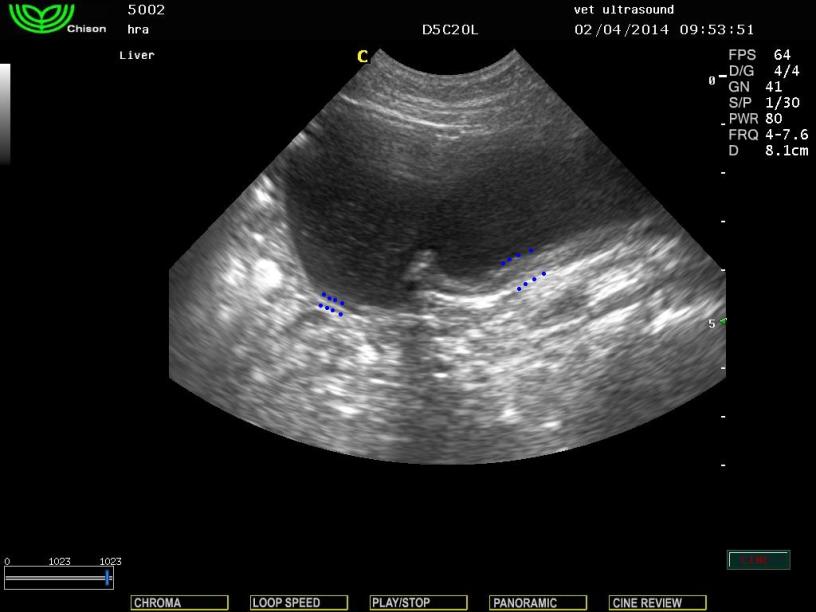

Στον υπερηχοτομογραφικό έλεγχο βρέθηκε εκκόλπωμα της ουροδόχου κύστης. Απώλεια του φυσιολογικού πάχους του τοιχώματος στο τμήμα του θόλου της ουροδόχου κύστης. Έγινε κυστεοκέντηση όπου και βρέθηκε αφθονία μικροβίων και φλεγμονικών κυττάρων. Μετά από ούρηση του ασθενή βρέθηκε πως το τμήμα που διέθεται φυσιολογικό πάχος, είχε αδειάσει ενώ το εκκόλπωμα είχε παραμείνει ίδιο σε μέγεθος. Κλινικά ο ασθενής δεν εκδήλωνε σημάδια ουρολοίμωξης. Λόγω του οτι δεν υπήρχαν συμπτώματα ο ιδιοκτήτης δεν θέλησε να προχωρήσει σε επιδιόρθωση του προβλήματος.

Σε ορισμένες προβολές φαίνεται σαν να είναι δύο ξεχωριστοί χώροι.

Οι διακεκομμένες γραμμές δείχνουν τη διαφορά στο πάχος στα δύο σημεία της ουροδόχου κύστης.